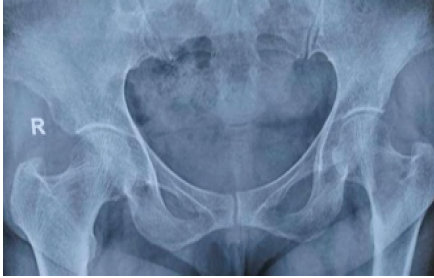

A 51-year-old female patient complained of pain; an X-ray of the left hip showed a lytic lesion on the neck of the femur, and an investigation showed HPT. She was advised to strictly avoid bearing weight for 6 weeks after the parathyroidectomy, and the lesion healed in 3 months (Fig. 2).

Figure 2: A 51-year-old female patient with a lytic lesion on the left trochanteric region.